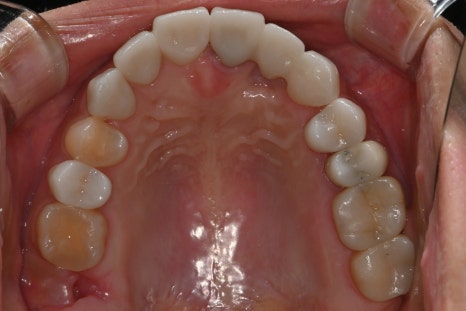

오른쪽 사진: “치료 후 윗니 안쪽 모습입니다. 보철물의 색상, 곡선, 위치까지 세심하게 맞춰 자연치처럼 복원되었습니다.”

이번 보철은 환자분의 얼굴형, 미소 습관, 잇몸 상태까지 고려해 맞춤 디자인되었으며,

치료 이후 전체적인 인상과 조화로움이 개선되었다는 피드백을 받았습니다.